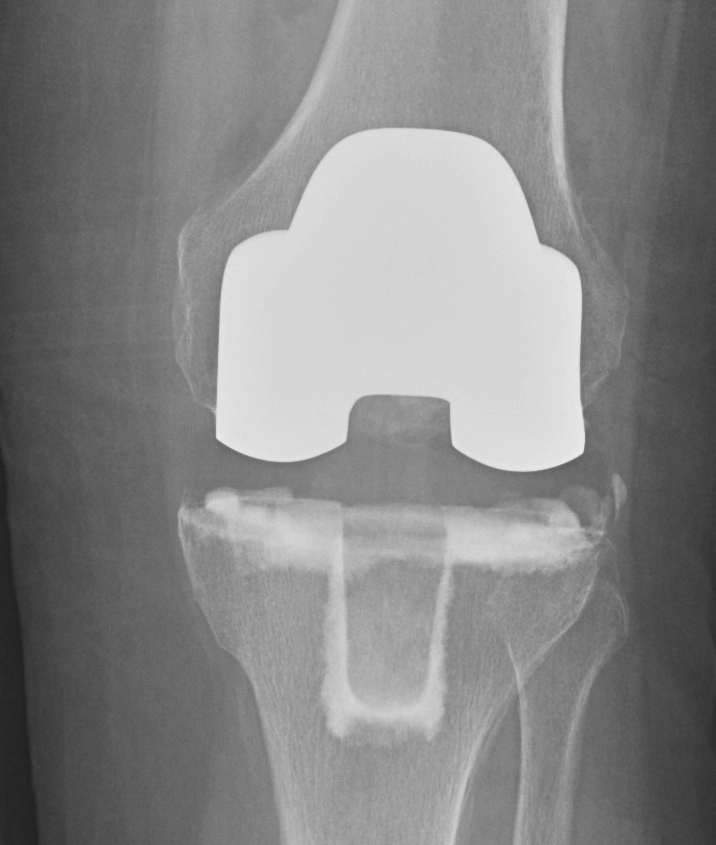

Tibia all poly v metal backed

All poly tibia

Advantage

- cheaper (by $2000)

- good in elderly patients

- eliminates backside wear

Disadvantage

- lack of modularity

- difficult to insert if PS

Metal backed

- improved load distribution

- modularity improves revision options (i.e. poly exchange)

- modularity enables increasing trialling before definitive implants

- problems with locking mechanism

- most have some micromotion

- potential for backside wear / increased particulate debris